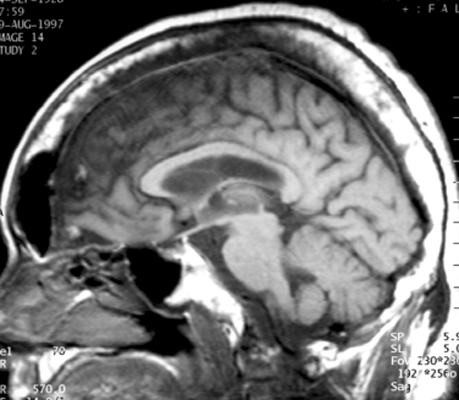

Diagnosis:Paget's Disease Discussion:Plain film of the skull reveals a large mottled area of radiolucency with small areas of increased density within it. The MR image of the skull reveals a thickened, enlarged cranium with increase in the marrow space. Two bone scan images also reveal increased activity in the skull, more localized to one side, characteristic to the localized disease seen in Paget's. This is classic cranial involvement of Paget's. In the cranium, bone sclerosis may produce circular radiodense lesions in one area, whereas osteoporosis circumscripta is noted elsewhere. In the skull, the common region of involvement is the cranial vault. The osteolytic phase is called osteoporosis circumscripta and appears as multiple geographic, well-demarcated regions of bone resorption that may be mistaken for metastases. Focal radiodensities occur as pagetoid bone is formed. In the quiescent phase, there is a radiodense cotton-wool appearance with a thickened vault. References: